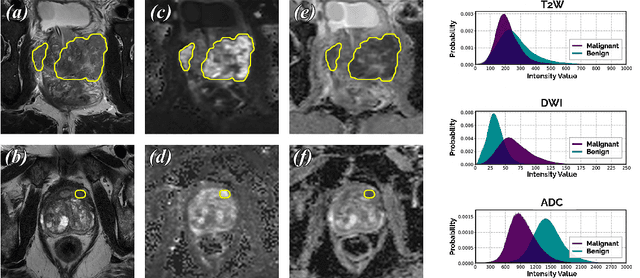

End-to-end Prostate Cancer Detection in bpMRI via 3D CNNs: Effect of Attention Mechanisms, Clinical Priori and Decoupled False Positive Reduction

We present a novel multi-stage 3D computer-aided detection and diagnosis (CAD) model for automated localization of clinically significant prostate cancer (csPCa) in bi-parametric MR imaging (bpMRI). Deep attention mechanisms drive its detection network, targeting multi-resolution, salient structures and highly discriminative feature dimensions, in order to accurately identify csPCa lesions from indolent cancer and the wide range of benign pathology that can afflict the prostate gland. In parallel, a decoupled residual classifier is used to achieve consistent false positive reduction, without sacrificing high sensitivity or computational efficiency. Furthermore, a probabilistic anatomical prior, which captures the spatial prevalence of csPCa as well as its zonal distinction, is computed and encoded into the CNN architecture to guide model generalization with domain-specific clinical knowledge. For 486 institutional testing scans, the 3D CAD system achieves $83.69\pm5.22\%$ and $93.19\pm2.96\%$ detection sensitivity at 0.50 and 1.46 false positive(s) per patient, respectively, along with $0.882$ AUROC in patient-based diagnosis $-$significantly outperforming four state-of-the-art baseline architectures (U-SEResNet, UNet++, nnU-Net, Attention U-Net) from recent literature. For 296 external testing scans, the ensembled CAD system shares moderate agreement with a consensus of expert radiologists ($76.69\%$; $kappa=0.511$) and independent pathologists ($81.08\%$; $kappa=0.559$); demonstrating strong generalization to histologically-confirmed malignancies, despite using 1950 training-validation cases with radiologically-estimated annotations only.